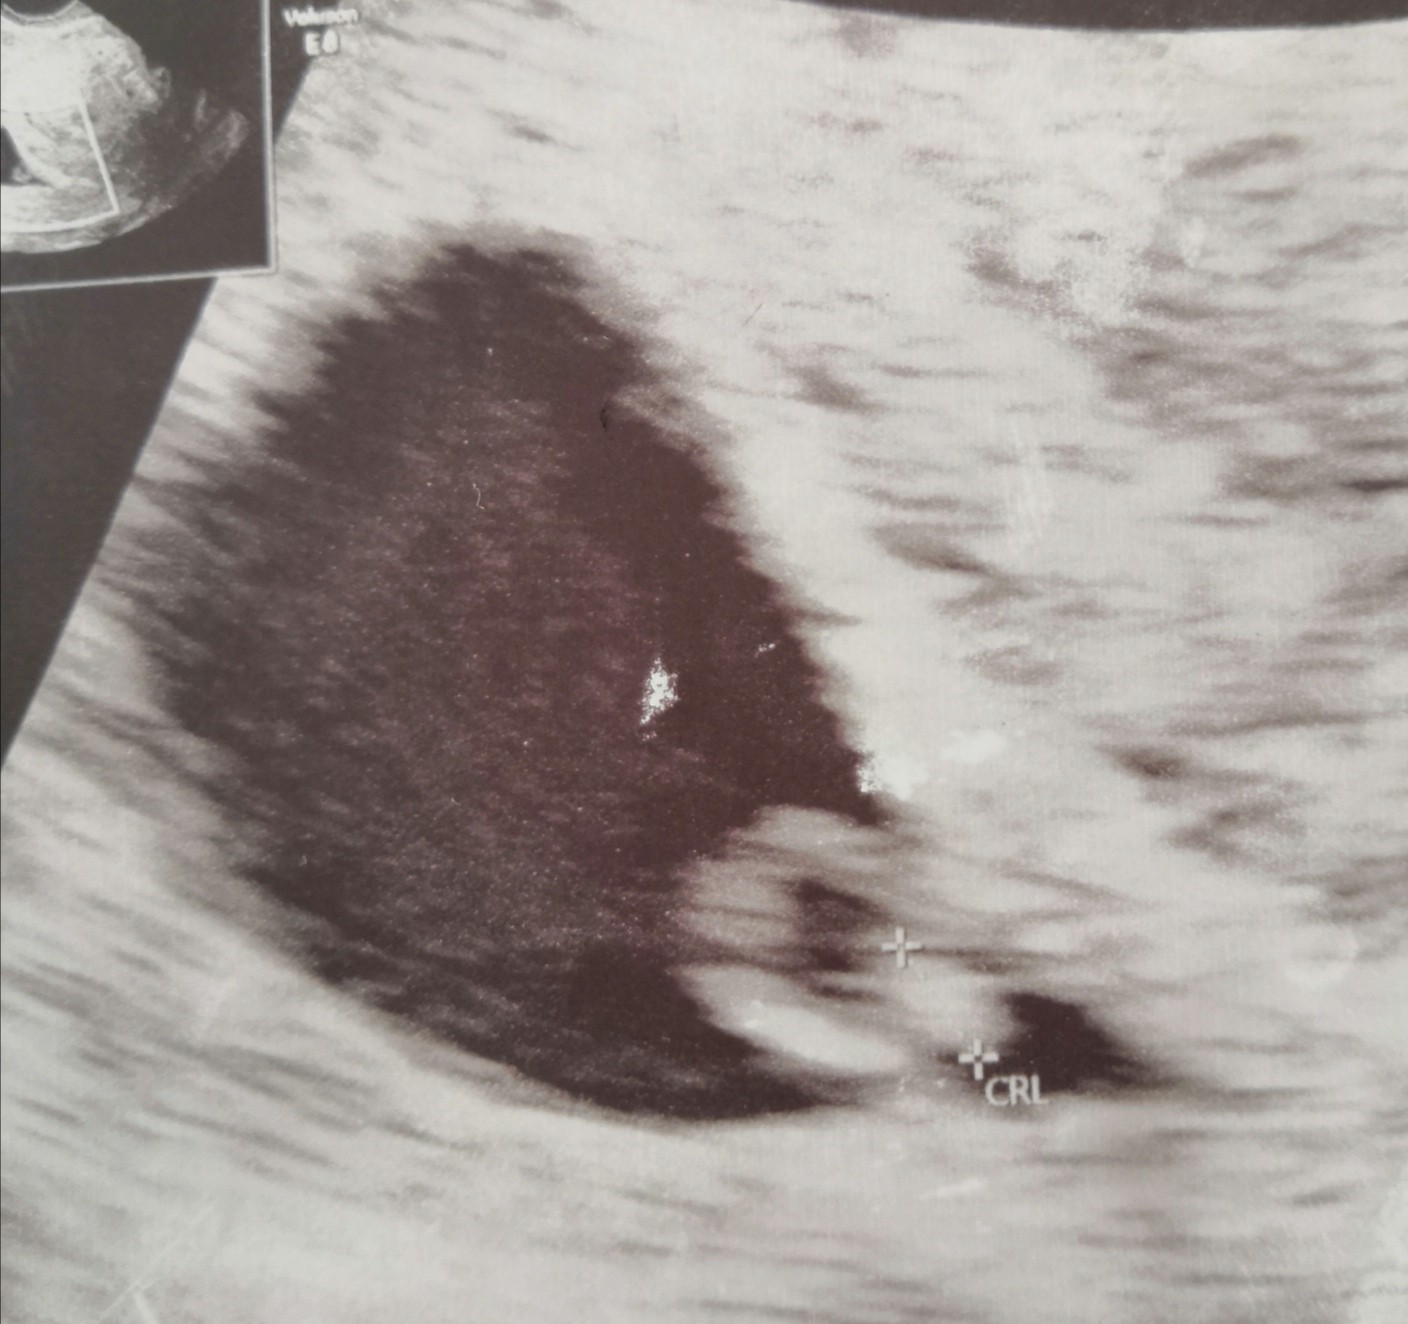

Dzisiaj byłam na wizycie 5+3, widać pęcherzyk żółtkowy i ogólnie mówi że aktualnie wszystko poprawnie. Kolejna wizyta za 2 tyg może będzie bicie serca 🤞😊Zobacz załącznik 1287549

piękna fasolka, trzymamy kciuki za serduszko ❤️